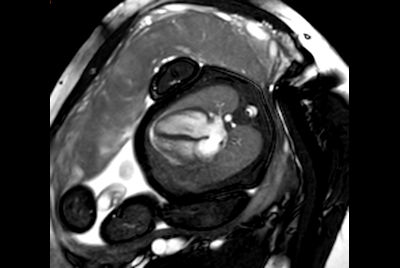

Fetal Cardiac with smart-sync

Cardiac imaging with Compressed SENSE

30 minute Cardiac Function and Fibrosis at 1.5T

30 minute Cardiac Function and Fibrosis at 3.0T

Cardiac MRI at 3.0T